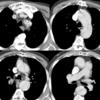

Ao Diss 2a

Date: 12/31/2004

Views: 3718